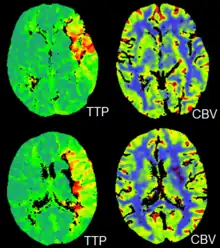

CT perfusion imaging

CT perfusion imaging is a specific form of CT to assess flow through blood vessels whilst injecting a contrast agent.[19] Blood flow, blood transit time, and organ blood volume, can all be calculated with reasonable sensitivity and specificity.[19] This type of CT may be used on the heart, although sensitivity and specificity for detecting abnormalities are still lower than for other forms of CT.[20] This may also be used on the brain, where CT perfusion imaging can often detect poor brain perfusion well before it is detected using a conventional spiral CT scan.[19][21] This is better for stroke diagnosis than other CT types.[21]